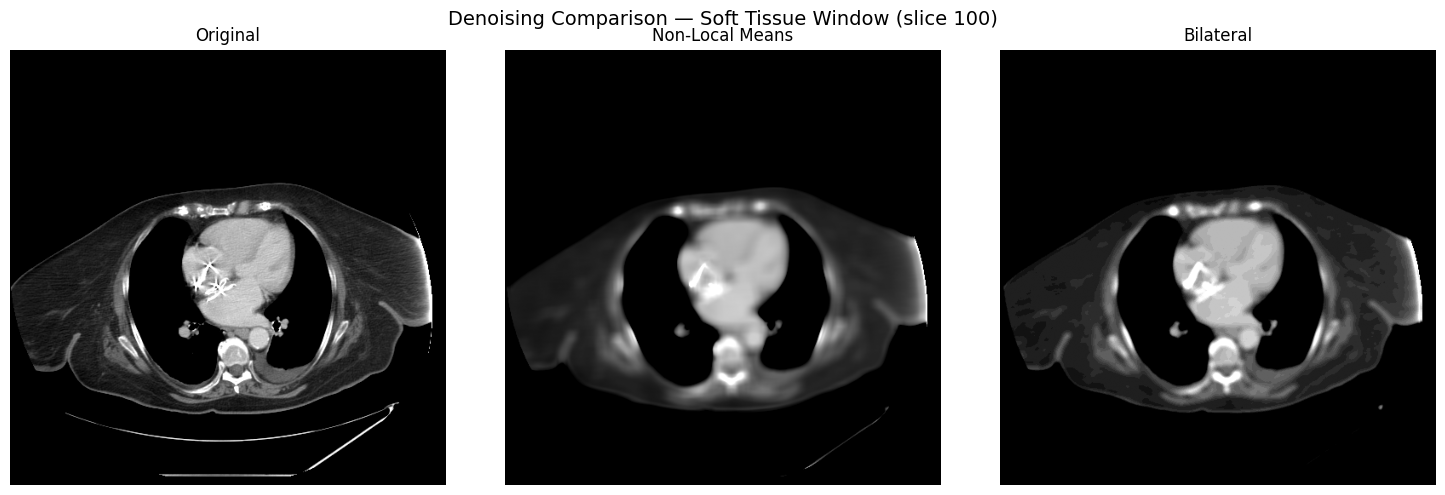

Denoising Methods

Compare non-local means and bilateral denoising on a single slice, viewed through the soft-tissue window:

denoising.py

tissue_slice = image[SLICE_CARINA]

nlm_denoised = processor.denoise(tissue_slice, method="nlm")

bilateral_denoised = processor.denoise(tissue_slice, method="bilateral")

fig, axes = plt.subplots(1, 3, figsize=(15, 5))

for ax, img, title in zip(

axes,

[tissue_slice, nlm_denoised, bilateral_denoised],

["Original", "Non-Local Means", "Bilateral"],

):

windowed = processor.apply_window(img, window="soft_tissue")

ax.imshow(windowed, cmap="gray")

ax.set_title(title)

ax.axis("off")

Original vs non-local means vs bilateral denoising